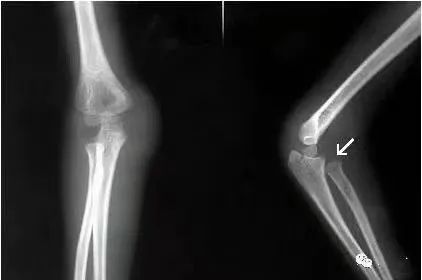

(6)肱骨髁上骨折

肱骨外髁骨折:肿胀及压痛局限于肘外侧,有时可触及骨折块;X片摄片桡骨纵轴线不通过肱骨小头骨化中心。

肱骨髁上骨折:肿痛较明显,呈环周压痛;X线片示骨折线不波及关节面,桡骨纵轴线通过肱骨小头骨化中心。

肱骨小头骨折:单纯的肱骨小头骨折多见于成人,合并部分外髁的肱骨小头骨折以儿童多见。亦有肘外侧及肘部的肿胀、疼痛,功能障碍;肘关节伸屈活动受限,尤其屈曲90-100°,常发生肘部疼痛加重并有阻力感觉;X线表现常有特征性,需仔细观察正、侧位X线片。